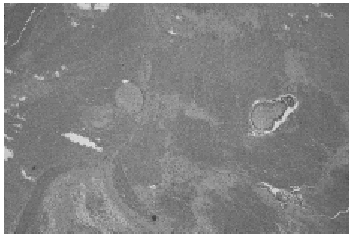

Posteriormente se realizó el legrado uterino, con el que se obtuvo abundante material. La paciente fue dada de alta a las 48 h. El examen histológico evidenció en el tejido asignado como fragmento ovárico material con cuerpos albicans y numerosas vellosidades coriales revestido por cito y sincitiotrofoblasto, y en la biopsia endometrial, endometrio con transformación decidual y signos de Arias-Stella.